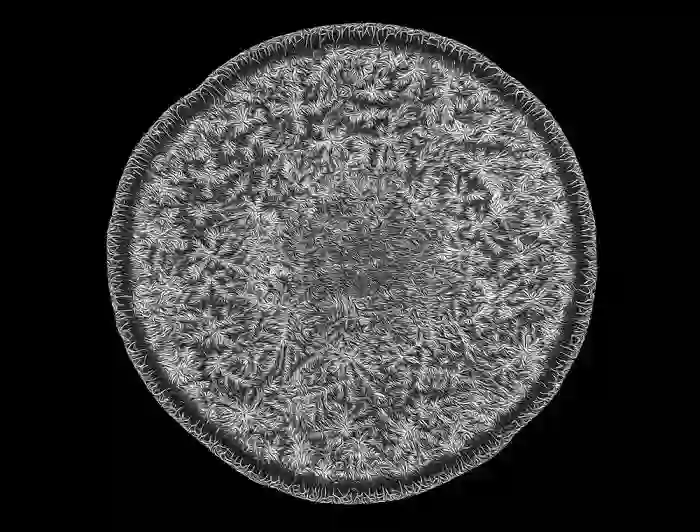

乳腺组织

第17名:哺乳期的乳腺组织(Caleb Dawson/ 摄)Caleb Dawson来自澳大利亚墨尔本干细胞和癌症系沃尔特和伊丽莎霍尔医学研究所